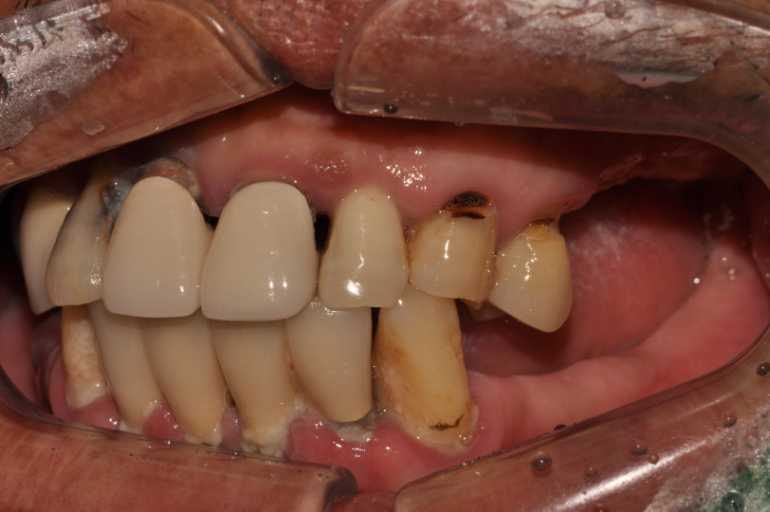

고정형 무치악 임플란트 전후 사례

무치악 임플란트 전후 실제 사례 #1, #2

이미지 위에 가운데 동그라미를 클릭한 상태에서 왼쪽 또는 오른쪽으로 드래그해보세요! 드래그할 때마다 환자의 전후 변화를 확인하실 수 있습니다.

#무치악 임플란트 환자 사례 : 임플란트로 찾은 새로운 미소